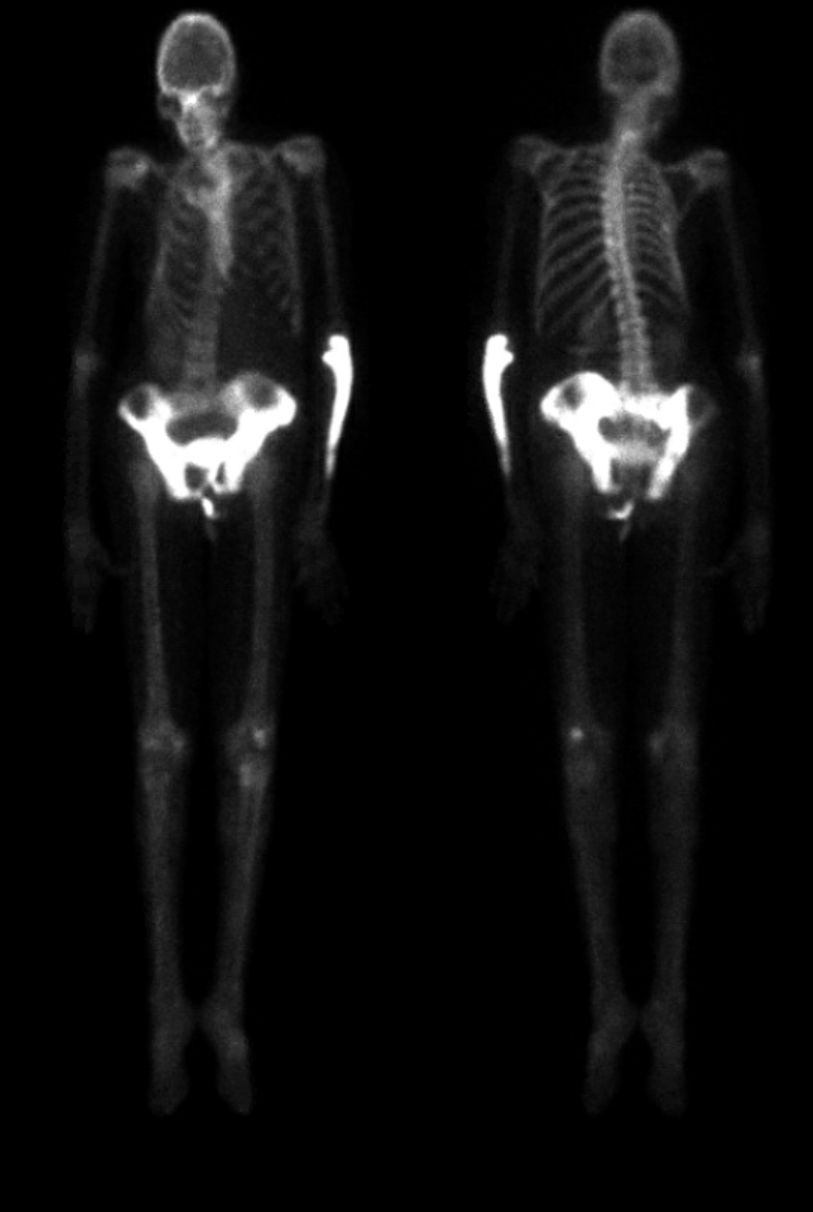

Radshare PAGET'S DISEASE

Paget disease bone scan Radiology Case Paget's Disease Long Bones Radiology A constellation of characteristic radiographic features in paget disease of bone comprising epiphyseal. Diagnosis of paget disease, evaluating the type and extent of complications, and monitoring the effects of therapy. The following recommendations were identified as the most important: 1) radionuclide bone scans, in addition to targeted radiographs, are. Paget’s disease of bone is a metabolic remodeling bone disorder that. Paget's Disease Long Bones Radiology.